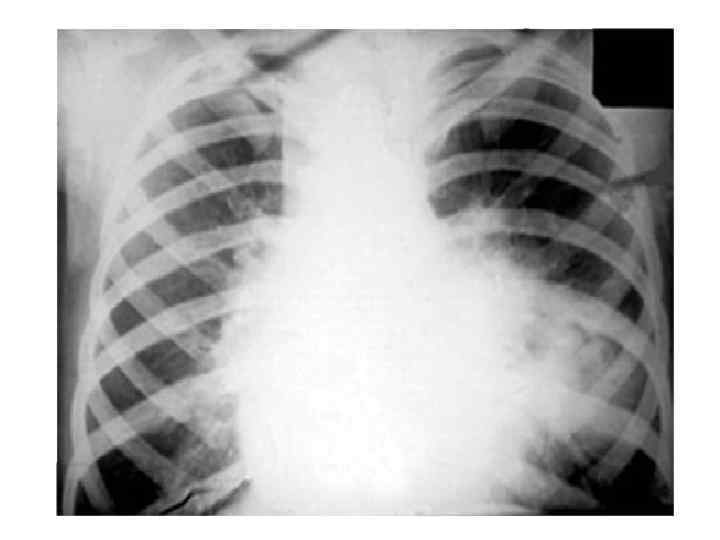

Варианты течения ТВГЛУ 1) с неосложнённым течением, 2) с осложнённым течением. • Клиническая картина неосложнённого ТВЛУ характеризуется симптомами интоксикации и наблюдается в современных условиях у 85% больных (В. А. Соколов). Рентгенологическая картина обусловлена изменениями корней лёгких, реже – средостения, при вовлечении в процесс нескольких групп ВЛУ. • Клиническая и рентгенологическая картина осложнённого ТВЛУ, характеризуется вовлечением в процесс бронхов, плевры, лёгких.